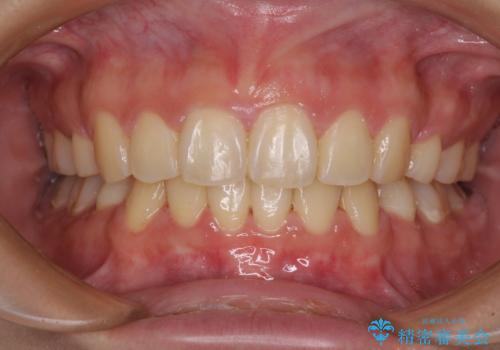

部分矯正で出っ歯になった 出っ歯改善の抜歯矯正

- 上下前歯を部分矯正したところ出っ歯になってしまったとのことで来院された患者様です。

上下左右第一小臼歯4本を抜歯して、積極的に口元を引っ込めるよう、ワイヤー装置にて矯正治療を行うこととしました。

治療後には口が閉じやすくなり、患者様には大変満足していただきました。